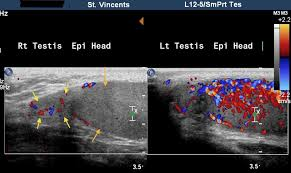

image of epididymo-orchitis

sonographic findings of epididymo-orchitis

epididymis appears as enlarged, hypoechoic gland

if secondary hemorrhage has occurred, epididymis may contain focal hyperechoic areas

hyperemic flow confirmed with color doppler